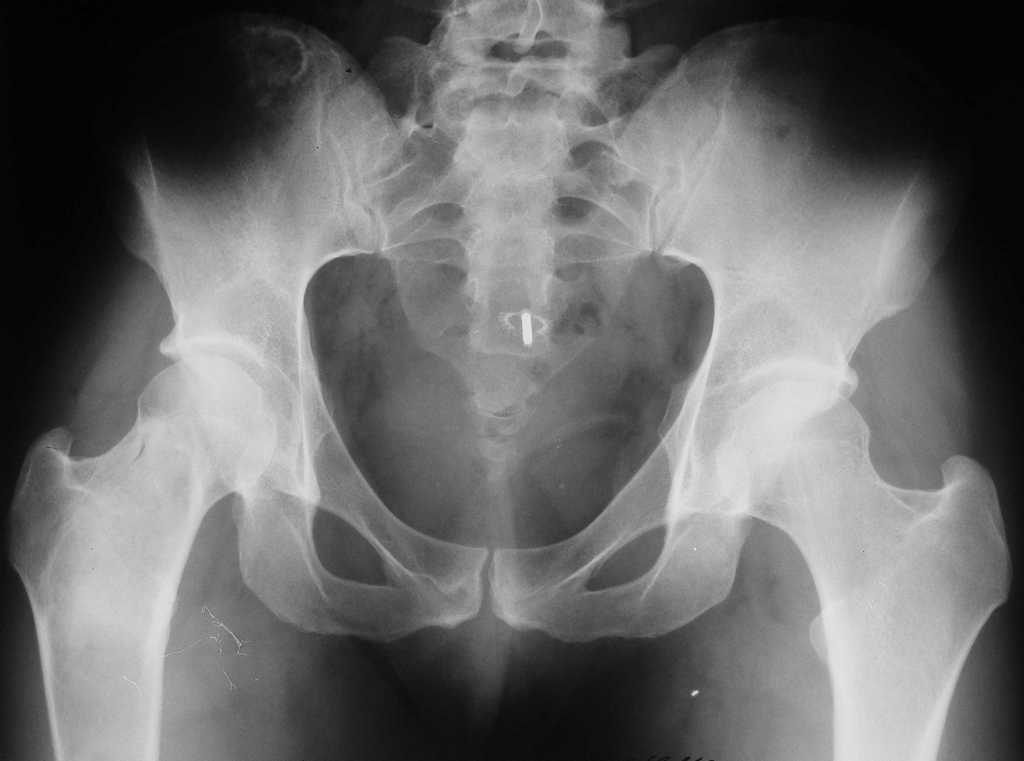

Уважаемые коллеги! В клинику поступила молодая женщина 35 лет с

жалобами на интенсивные боли в области правого бедра, носят спонтанный

характер, имеются "ночные" боли. Движения в правом тазобедренном

суставе в полном объёме, практически безболезненные. По результатам

x-ray диагностики выявлен патологический очаг, занимающий весь

проксимальный отдел и 2/3 диафиза правой бедренной кости. Другие

трубчатые кости верхних и нижних конечностей - без очагов поражения.

Имеется небольшой (1,5х2,5 см) очаг в крыле правой подвздошной кости.

По результатам трепанобиопсии проксимального отдела правой бедренной

кости - фиброзная строма и костные балки, без атипии.